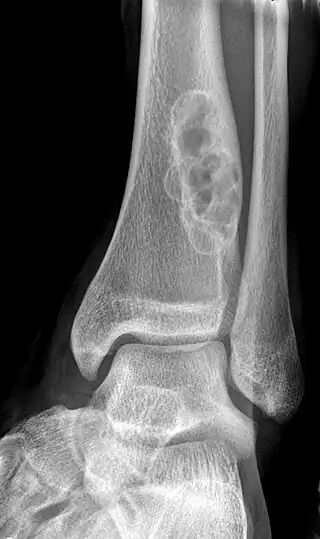

Diagnosis is by X-ray or MRI, usually when investigating a person for something else.[3] Medical imaging typically shows a well marginated radiolucent lesion, with a distinct multilocular appearance, sometimes looking like bubbles.[3] It is usually around 1-2cm in size, but be as large as 7cm.[4] They consist of foci consist of collagen rich connective tissue, fibroblasts, histiocytes and osteoclasts.[3] Usually no treatment is required.[4] Surgical curettage and bone grafting may be required if it is large.[4]

It is usually iagnosed by x-ray or MRI, when investigating another problem.[1] The tumor presents as a well defined radiolucent lesion, with a distinct multilocular appearance, sometimes looking like a "soap bubble".[2] If small and no symptoms, then biopsy is not needed.[1]

1. a. Front view X-ray: NOF of the lower leg bone near ankle, with well-defined tumor

1. b. Side view X-ray: NOF of the lower leg bone near ankle, with well-defined tumor